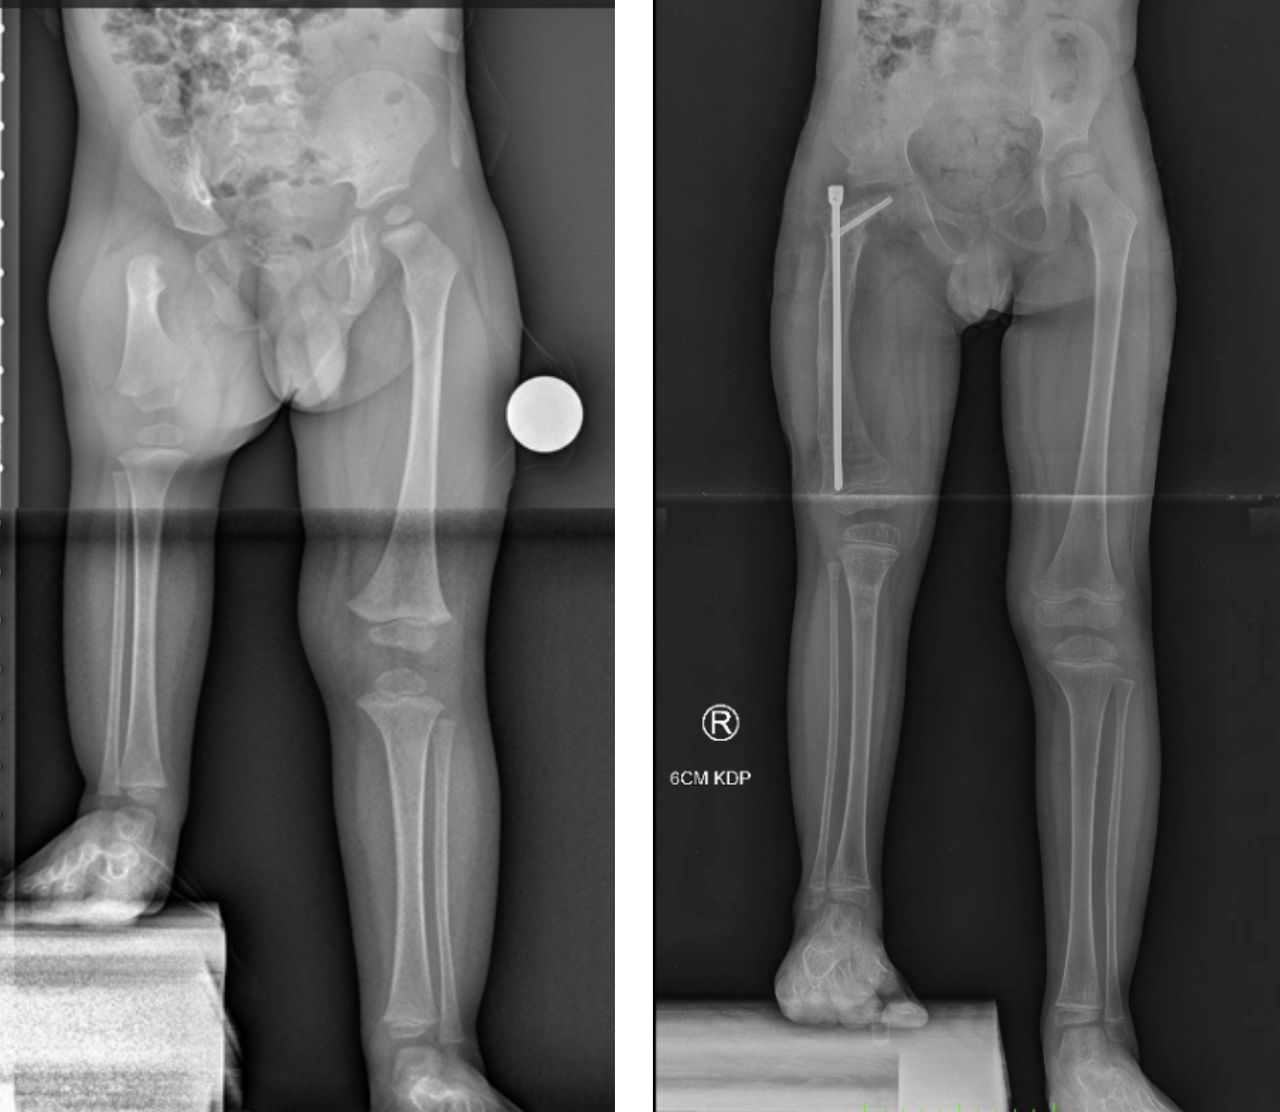

Jestem chirurgiem specjalizującym się w zaawansowanych rekonstrukcjach stawów oraz wydłużaniu kończyn dolnych (limb lengthening and reconstruction surgery). Kompleksowo opiekuję się osobami z problemami o podłożu ortopedycznym oraz neurologicznym, szczególnie dzieci z wadami wrodzonymi i schorzeniami nerwowo-mięśniowymi. Dzięki wieloletniemu doświadczeniu w nowoczesnych technikach rekonstrukcyjnych znacząco udoskonaliłem metody chirurgicznego leczenia dzieci z problemami neurologicznymi, otwierając przed nimi nowe możliwości poprawy funkcjonalności oraz jakości życia. Specjalizujemy się w jednoczasowych wielopoziomowych rekonstrukcjach kończyn (SEMLS) oraz kompleksowych rekonstrukcjach stawów biodrowych, łącząc sprawdzone techniki operacyjne z innowacyjnymi rozwiązaniami. Oprócz leczenia operacyjnego, koordynuje leczenie zachowawcze, obejmujące wielopoziomowe podania toksyny botulinowej (BTX) oraz minimalnie inwazyjne procedury, takie jak SPML (Selective Percutaneous Myofascial Lengthening) czy PERCS (Percutaneous Muscle Lengthening). Każdy pacjent otrzymuje indywidualnie opracowany program terapeutyczny, którego celem jest osiągnięcie najlepszych efektów przy minimalnym obciążeniu. Opiekuję się również pacjentami dorosłymi wymagającymi endopiotezoplastyki stawów oraz ratowaniem kończyn przed amputacją z powodu aktywnej lub przewlekłej infekcji W mojej pracy kluczowe jest podejście holistyczne, które łączy zaawansowane techniki chirurgiczne z terapią zachowawczą, aby zapewnić pacjentom kompleksową opiekę oraz trwałe efekty leczenia. Powierzenie nam zdrowia pacjentów jest dla nas ogromną odpowiedzialnością, a jednocześnie najwyższym zaszczytem. Zakres mojej specjalizacji obejmuje leczenie: 1. Wady wrodzone i rozwojowe kończyn: Hemimelia strzałkowa, niedorozwój kości udowej (CFD – Congenital Femoral Deficiency) – zaawansowane metody rekonstrukcyjne, w tym wydłużanie oraz procedury typu SUPERhip, SUPERankle Brak kości promieniowej i inne deformacje kończyny górnej – zabiegi ulnaryzacji, pollicyzacji, korekcji osi Mnogie wyrośla chrzęstno-kostne (MHE) – chirurgiczna korekcja deformacji i zapobieganie wtórnym ograniczeniom ruchomości Wrodzony staw rzekomy kości piszczelowej (CPT) – rekonstrukcja podudzia metodą CPT Xunion 2. Zaburzenia osi i długości kończyn: Skrócenia kończyn – techniki wydłużania z zastosowaniem gwoździ teleskopowych, aparatów Ilizarowa oraz STRYDE i PRECICE Zaburzenia osi kończyn (koślawość, szpotawość, rotacje) – korekcje wielopłaszczyznowe, osteotomie oraz stabilizacja z użyciem aparatów zewnętrznych i gwoździ wewnętrznych 3. Neuroortopedia – leczenie pacjentów z zaburzeniami neurologicznymi: Mózgowe porażenie dziecięce (MPD) – operacje zmniejszające spastyczność, korekcje stawów oraz zabiegi wielopoziomowe poprawiające funkcję chodu Przepuklina oponowo-rdzeniowa (spina bifida) – leczenie deformacji stóp i kończyn dolnych, stabilizacja stawów Artrogrypoza – wieloetapowe leczenie chirurgiczne poprawiające zakres ruchu i funkcjonalność kończyn 4. Zakażenia i zaburzenia zrostu kostnego: Osteomyelitis (zakażenia kości i szpiku) – leczenie chirurgiczne i antybiotykoterapia celowana Zaburzenia zrostu kostnego, brak zrostu (non-union, mal-union) – nowoczesne techniki transportu kostnego, przeszczepów i stabilizacji 5. Rekonstrukcja dużych stawów i leczenie deformacji: Endoprotezoplastyka biodra, kolana i stawu skokowego – zarówno w przypadkach zwyrodnieniowych, jak i pourazowych Choroba Legg-Calvé-Perthesa – metody operacyjne poprawiające ukrwienie głowy kości udowej i ograniczające deformację Złuszczenie głowy kości udowej (SCFE – Slipped Capital Femoral Epiphysis) – leczenie za pomocą zmodyfikowanej metody Dunna, pozwalającej na anatomiczną rekonstrukcję biodra i zachowanie funkcji stawu Dysplazje szkieletowe – interdyscyplinarne podejście do leczenia deformacji i ograniczeń funkcjonalnych 6. Leczenie stopy cukrzycowej i deformacji stóp: Stopa cukrzycowa – nowoczesne techniki rekonstrukcji stopy, zapobieganie amputacji Deformacje stopy (np. stopa końsko-szpotawa, płasko-koślawa, stopa sierpowata) – korekcja chirurgiczna i indywidualne podejście do biomechaniki chodu 7. Chirurgia urazowa dzieci i dorosłych: Leczenie złamań z zastosowaniem minimalnie inwazyjnych technik operacyjnych Rekonstrukcja kończyn po urazach, w tym ratowanie kończyny zagrożonej amputacją Stabilizacja wewnętrzna i zewnętrzna złamań patologicznych oraz pourazowych 8. Osseointegracja - zaopatrzenie pacjentów po amputacji poprzez korekcję kikuta lub aplikację osseointegracji do kości powyżej lub poniżej kolana wraz z zaopatrzeniem prtotetycznym 9. Wydłużanie kosmetyczne kończyn dolnych i górnych. Wykonujemy jednoczasowe operacje zarówno wydłużania kości udowych i piszczelowych jako jedyny ośrodek w Europie. Efekt jaki możemy uzyskać to 10-12 cm zwiększenia wzrostu. Wierzę, że najlepsze efekty leczenia można osiągnąć dzięki współpracy grona specjalistów, kierując się zasadą pacjentocentryzmu, która stawia potrzeby pacjenta w centrum procesu terapeutycznego.. Dlatego każda konsultacja odbywa się w interdyscyplinarnym zespole, w skład którego wchodzą ortopedzi, fizjoterapeuci, ortotycy i terapeuci zajęciowi. Pierwsza wizyta trwa około 1,5 godziny i obejmuje szczegółową ocenę stanu zdrowia oraz opracowanie planu leczenia chirurgicznego. W naszym instytucie działamy na podstawie indywidualnie opracowanych dla każdej jednostki chorobowej protokołów leczenia operacyjnego oraz postępowania fizjoterapeutycznego, których jestem współautorem. Dzięki temu zapewniamy spójne, kompleksowe i skuteczne podejście terapeutyczne, dostosowane do specyfiki danej choroby i indywidualnych potrzeb pacjenta. Zapraszam na konsultacje ortopedyczne, neuroortopedyczne oraz deformacyjne.